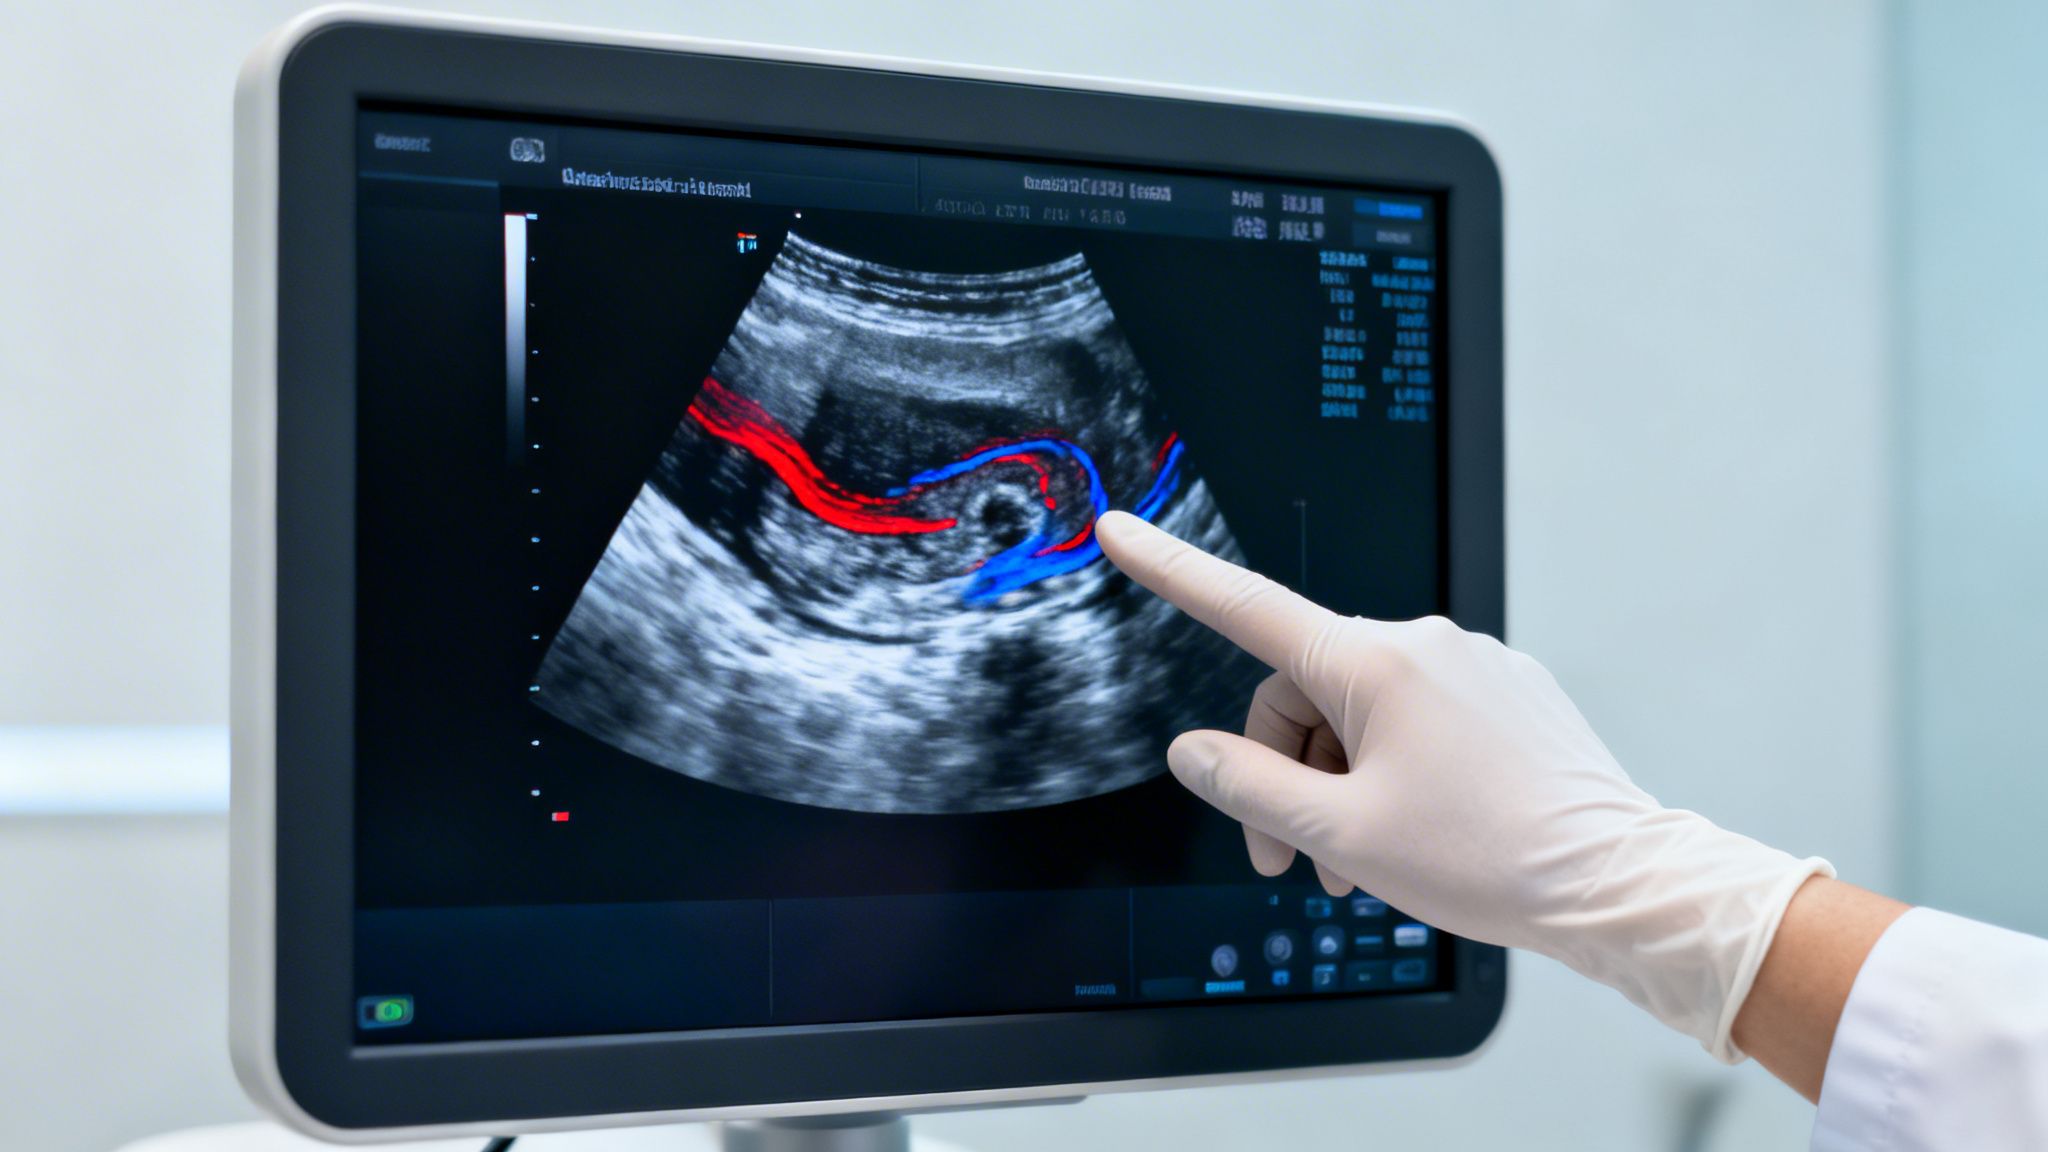

Når det specifikt gælder erektil dysfunktion, bruger jeg en særlig type ultralyd, der kaldes en Doppler-scanning. Denne teknik er fantastisk, fordi den lader mig måle både hastigheden og retningen på blodet, der strømmer gennem arterierne.

Jeg plejer at forklare det som en slags trafiktjek for blodårerne. Vi ser simpelthen efter, om der er "trafikpropper", der bremser blodets frie passage. En normal rejsning er fuldstændig afhængig af et sundt og uhindret blodflow, og scanningen giver os et klart svar.

Denne information er helt afgørende for vores plan. Viser scanningen, at blodforsyningen er nedsat, ved vi også, at shockwave-behandling kan være den rigtige strategi. Behandlingen stimulerer nemlig dannelsen af nye, små blodkar. Uden den viden ville vi famle i blinde.